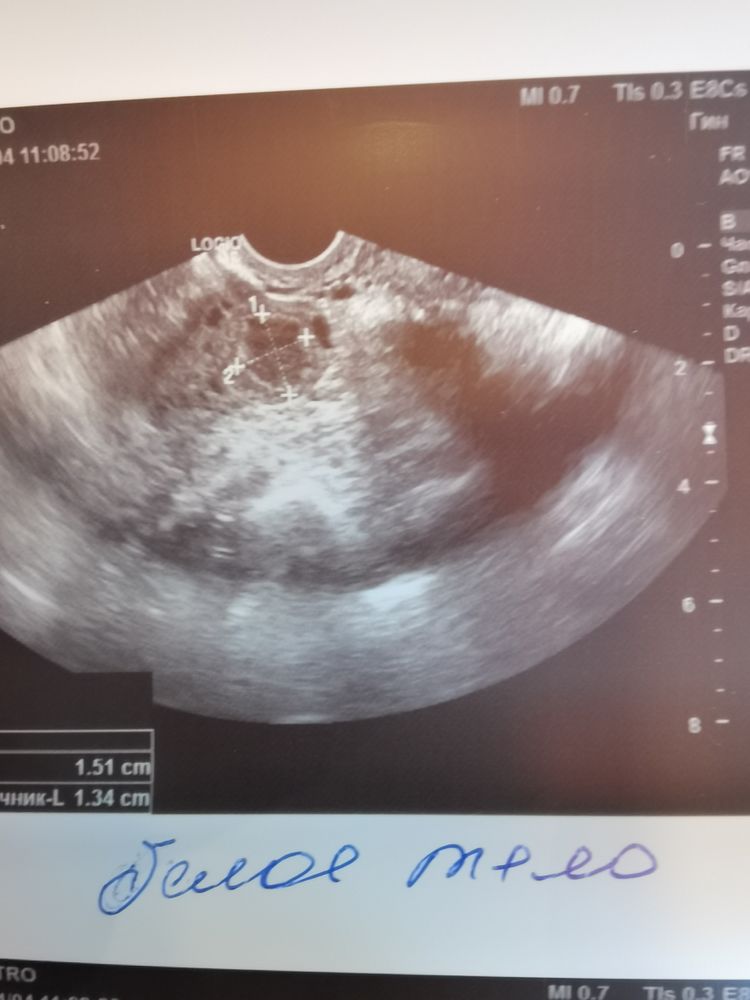

Да, ЖТ сдулось уже, превратилось в БТ, лютеина уже нет, ждать М 🤷‍♀️ По фото не понять, что именно это, размер какой БТ и эндика?

Изображение Виктория Север, размер 1,51 на 1.34. Эндик 9мм.

Ася Разманкина, у меня при Б такой же размер ЖТ был. Но эндометрий не беременный, увы. Хотя все бывает. Я сына на 6 мм зачала, может через неделю и эндик бы был всего 9 мм. Но, зато у вас свой цикл, это класс! Желаю скорейшего запузачивания!

Образуется на месте ЖТ. И да, беременности нет. ЖТ уходит.

Ангелина, тоесть я правильно понимаю, был доминантный лопнул, образовалась жт, и потом, так как зачатия не произошло оно превращается именно к концу цикла в бт? А если беременность, то продолжает жт работать. Всё так?

Ася Разманкина, да, жт работает и переходит в кисту